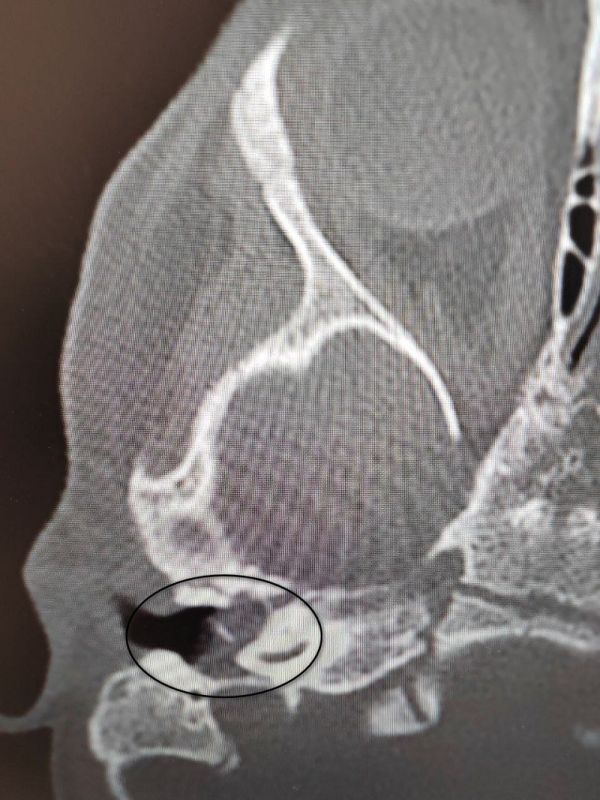

Малышка поступила в ВОДКБ №1 с правосторонним хроническим гнойным средним отитом и подозрением на врождённую холестеатому барабанной полости (кистозное патологическое образование в среднем ухе). Ей грозила потеря слуха.

Они решили оперировать малышку. Заведующий оториноларингологическим хирургическим отделением Антон Мащенко удалил холестеатому, провёл декомпрессию лицевого нерва и восстановил механизм звукопроведения. На пятый день после операции девочку выписали.